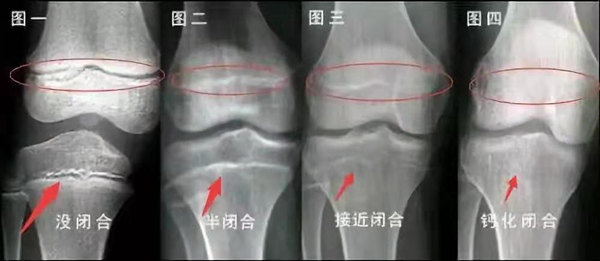

未成年時(shí)隨著年齡的增加骺軟骨端不斷骨化,骨骼就不斷增長。當(dāng)骨骺線完全閉合時(shí)骨骼就停止生長,個(gè)子也就不再增長了。一般骨骺端完全閉合的年齡是18~20歲左右。

青少年一般什么時(shí)候骨骺閉合?

一般女孩是在16歲,男孩是在18歲。

一般來說,女孩的骨齡超過14歲,男孩的骨齡超過16歲,這時(shí)其骨骺線已接近閉合,基本沒有長高的機(jī)會(huì)了。

因此,越早了解骨骺線閉合情況,越早干預(yù),孩子長高的可能性越大。